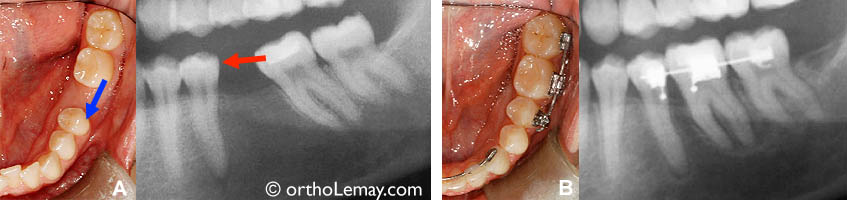

(A) Condition initiale avec la molaire supérieure allongée.

(B) Mini-vis d’ancrage et ressort utilisés pour “remonter” la dent.